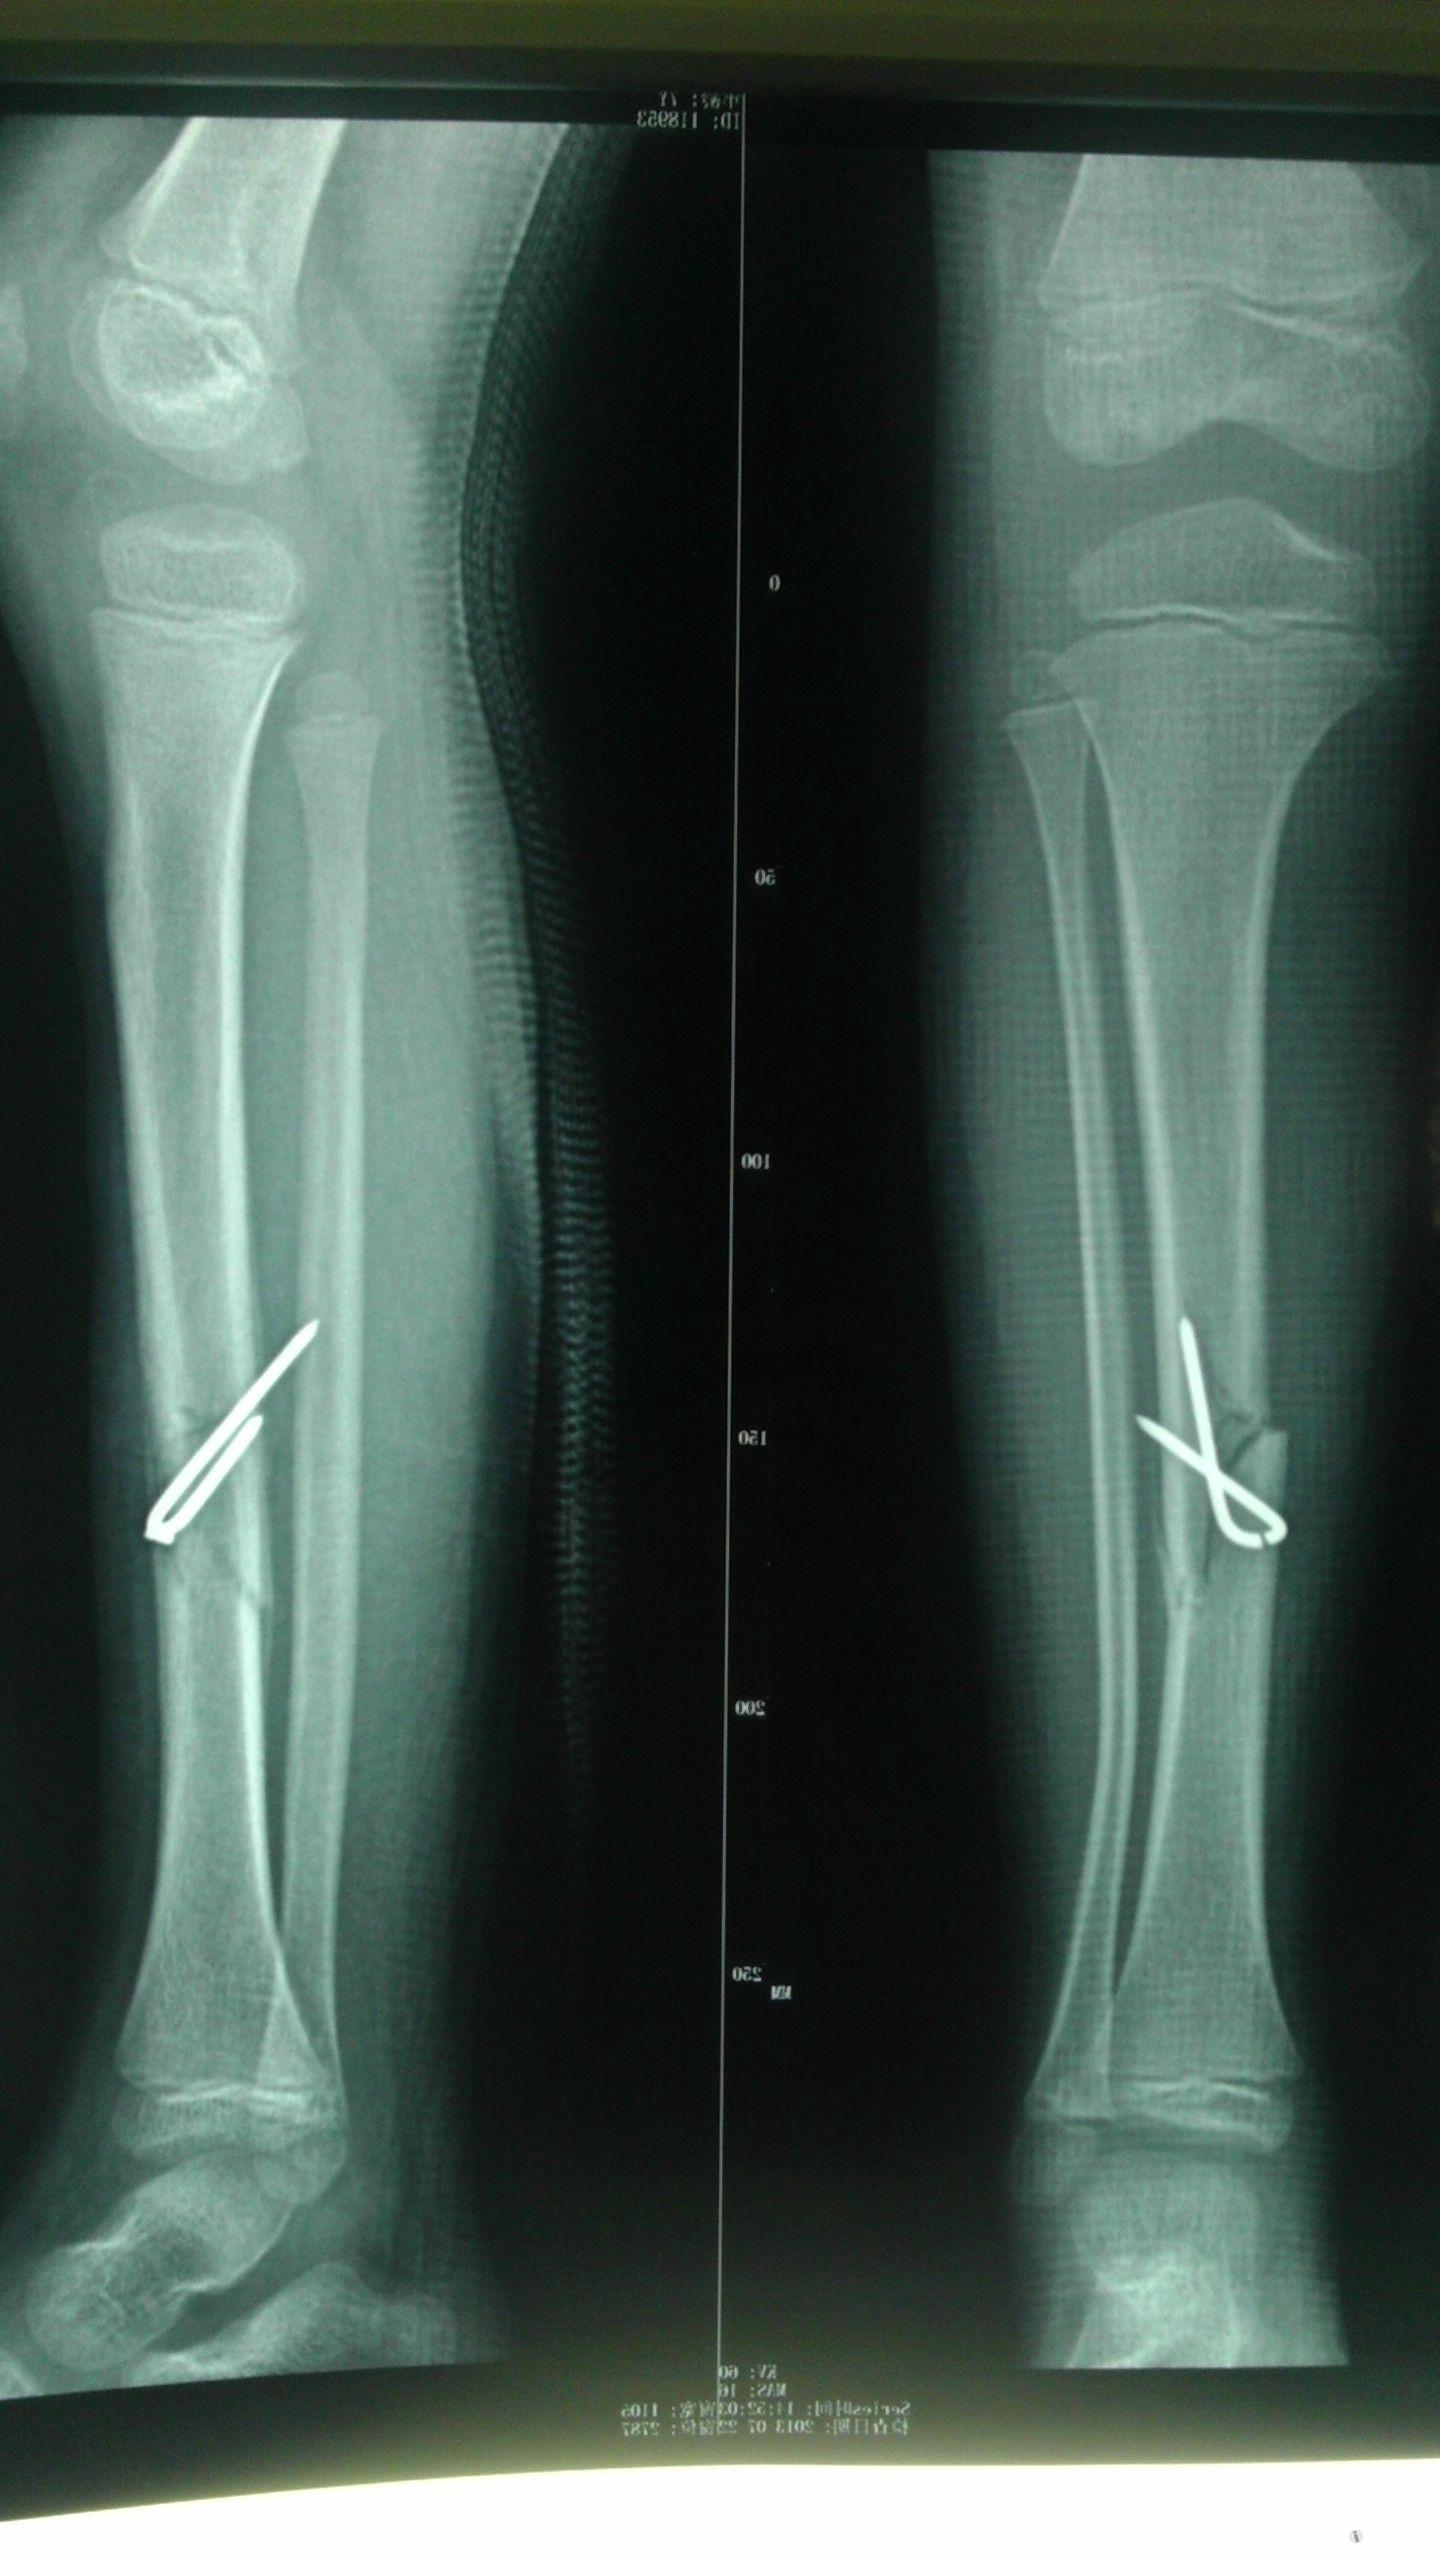

左侧胫腓骨x线照片